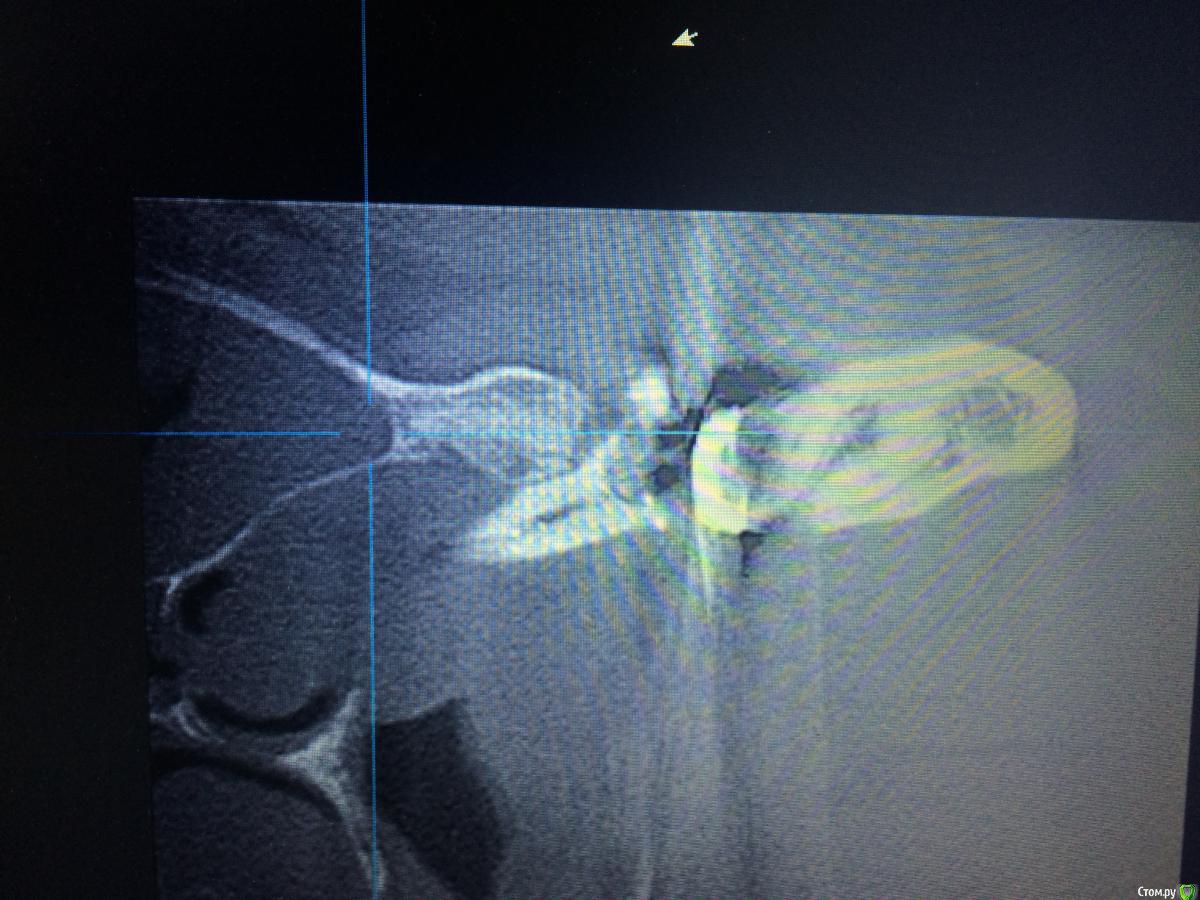

Shargik Опубликовано 23 октября, 2015 Поделиться Опубликовано 23 октября, 2015 Господа эндодонтисты, вот Вам такой случай.. Как думаете, стоит с ним повоевать, или сразу в плевашку? Беспокоит выбухание на небе и свищ с непрекращающимся гноетечением, каналы все проходимы, вот думаю, что с ним делать. Кто прилагается.. Ссылка на комментарий

Shargik Опубликовано 23 октября, 2015 Автор Поделиться Опубликовано 23 октября, 2015 Зуб 26, на небном корне обширный процесс. С небной стороны кости нет от слова совсем. В том то и дело, что пациент не сильно платёжеспособен, думается мне попробовать полечить, авось косточки хоть чуть вырастет, или думаете, это с мельницами бодаться.. Ссылка на комментарий